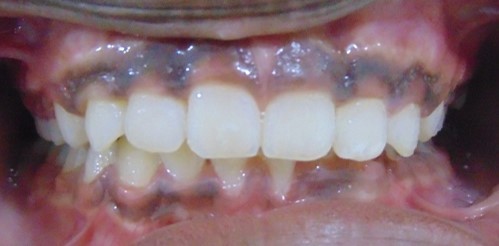

Before

After

Image 1